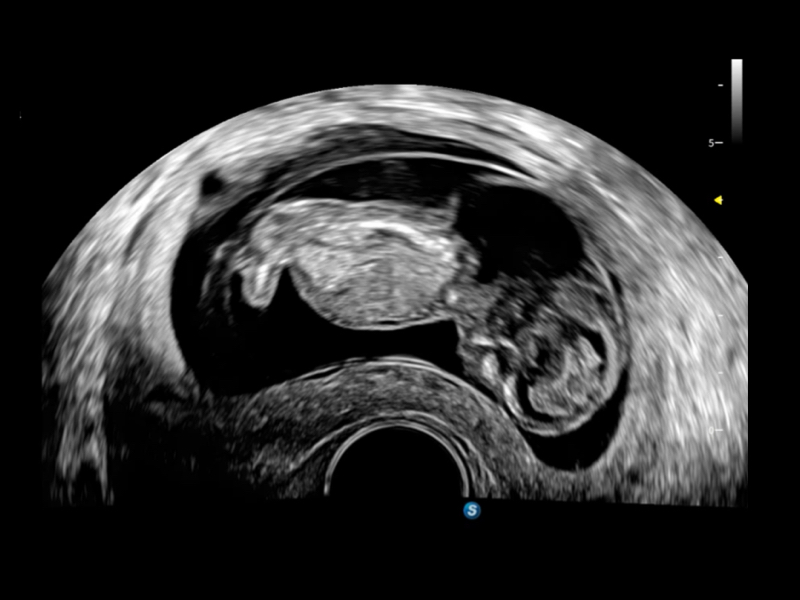

Entdecken Sie das Ultraschallsystem S70i Fenix – eine hochmoderne Lösung, die darauf ausgelegt ist, das Vertrauen zu stärken und die Effizienz in der Frauengesundheit zu maximieren. Mit seiner fortschrittlichen C-Field+™-Architektur bietet das S70i Fenix eine außergewöhnliche Bildqualität und intelligente klinische Lösungen für die Geburtshilfe und Gynäkologie – zur Förderung des Gesundheitsschutzes von Frauen.

Diese neuen Perspektiven ermöglichen die Betrachtung der Anatomie aus Volumenperspektiven, mit fortschrittlicher Bewertung und intelligenten Scan-Tools. Sie bieten Klinikern mehr Informationen und helfen, Anomalien früher als je zuvor zu identifizieren.

• S-Live Studio liefert eine brillante, realistische Hautvisualisierung in Echtzeit, indem es die Lichtausbreitung auf der Hautoberfläche simuliert und so die Tiefe und Authentizität des dreidimensionalen Bildes bereichert.